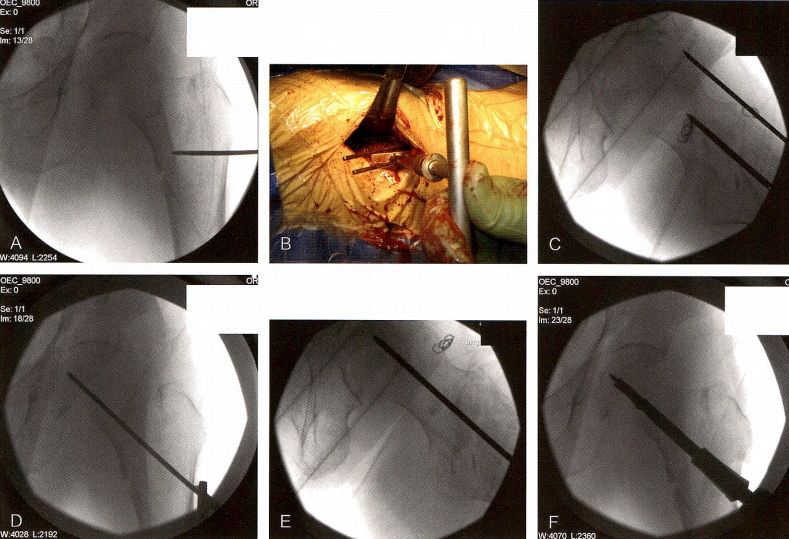

技术图1 骨折复位。A.术前的转子间骨折。B.纵向牵引后骨折位置。C.纵向牵引结合外展患肢后。D.纵向牵引、外展、内旋患肢后。E.骨折后沉,向后成角。F.纵向牵引、外展、内旋患肢,并在大腿下利用拐杖施加屈曲力后的骨折位置。G.术中大体照显示拐杖放置于远端骨块下。

将患者固定于牵引床上,施加轴向牵引,在冠状面上恢复骨折的长度,并部分纠正内翻畸形(技术图1)。外展患肢通常可以完全纠正内翻畸形,并恢复正常的颈干角。内旋远端肢体通常可以纠正骨折外旋畸形,内旋还可以使股骨颈平行于地面,以便帮助最终置人导针。有时需要外旋近端骨块才能纠正股骨旋转畸形。接着通过侧位片检查骨折的复位情况。通常,股骨远端骨折块后沉,近端骨折块受到髂腰肌牵拉呈屈曲向前。可在股骨干下放置一根拐杖支撑,也可以利用某些手术床上带软垫的支架来支撑大腿。通过正、侧位摄片再次评估骨折复位情况,并检查颈干角、股骨颈前倾角、旋转和股骨干的后沉,以此获得近似解剖的复位。可接受的复位质量标准是:力线正常或轻度外翻,侧位上成角<20,骨折平移<4mm"。如果无法获得近似解剖的闭合复位,可利用经皮技术,使用Schanz钉、骨钩或骨膜剥离器来操作骨折块。若复位程度仍然不够,必须采取切开复位。